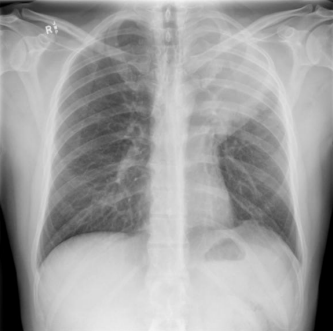

Homem de 30 anos, previamente hígido, farmacêutico, é atendido em ambulatório devido à queixa de tosse seca de mais de 6 meses de evolução. Buscou atendimento, pois vem tendo episódios de febre durante a noite, acompanhados de sudorese profusa, que cessam ao uso de dipirona. Durante anamnese, nega escarro produtivo, hemoptise, dor torácica ou dispneia, mas refere perda de peso discreta no período. No exame físico, evidencia-se adenomegalia de cerva de 2 centímetros em cadeia cervical anterior esquerda, pouco endurecida, aderida a planos profundos, sem sinais flogísticos, além de abaulamento discreto em fossa supraclavicular ipsilateral. Ausculta pulmonar com murmúrio vesicular reduzido, percussão com submacicez e frêmito toracovocal aumentado em ápice esquerdo, além de sibilos discretos em hemitórax esquerdo. Realizou a radiografia abaixo.

Enunciado 4938419-1

Com base no caso acima, a hipótese diagnóstica mais provável para o paciente é